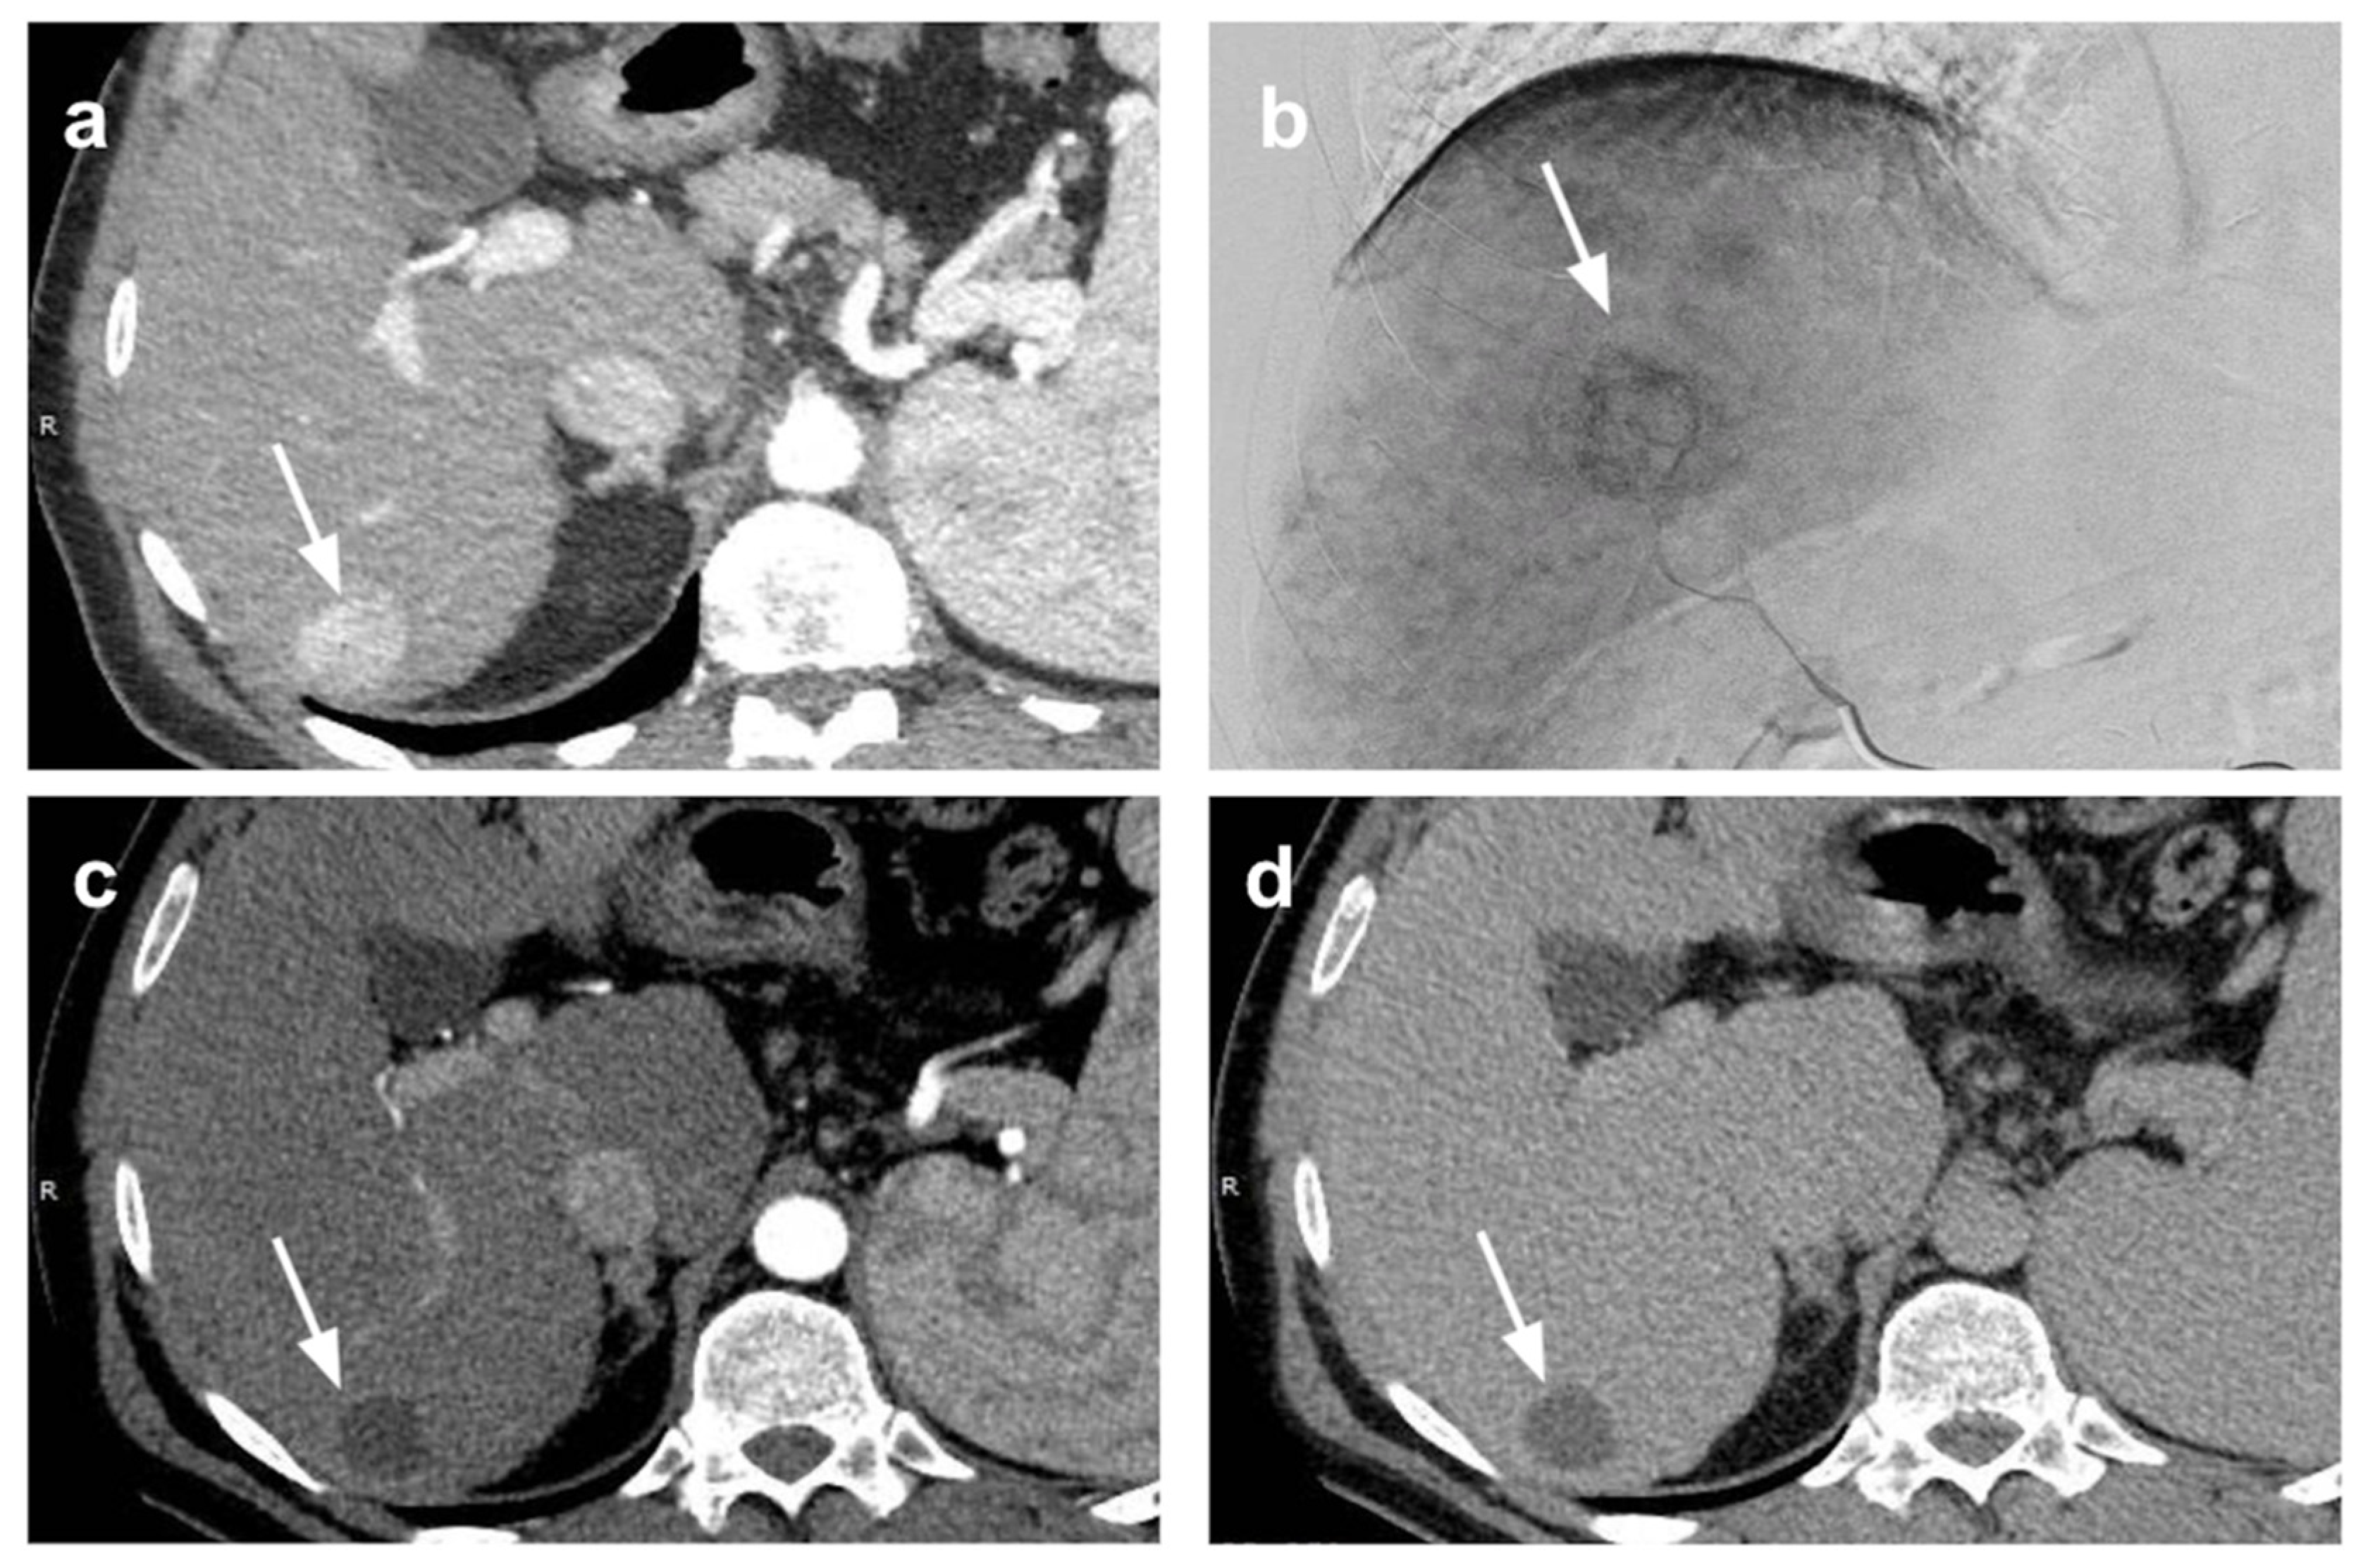

- Crocetti, L.; Scalise, P.; Bozzi, E.; Campani, D.; Rossi, P.; Cervelli, R.; Bargellini, I.; Ghinolfi, D.; De Simone, P.; Cioni, R. Microwave Ablation of Very-Early- and Early-Stage HCC: Efficacy Evaluation by Correlation with Histology after Liver Transplantation. Cancers 2021, 13, 3420. [Google Scholar] [CrossRef] [PubMed]